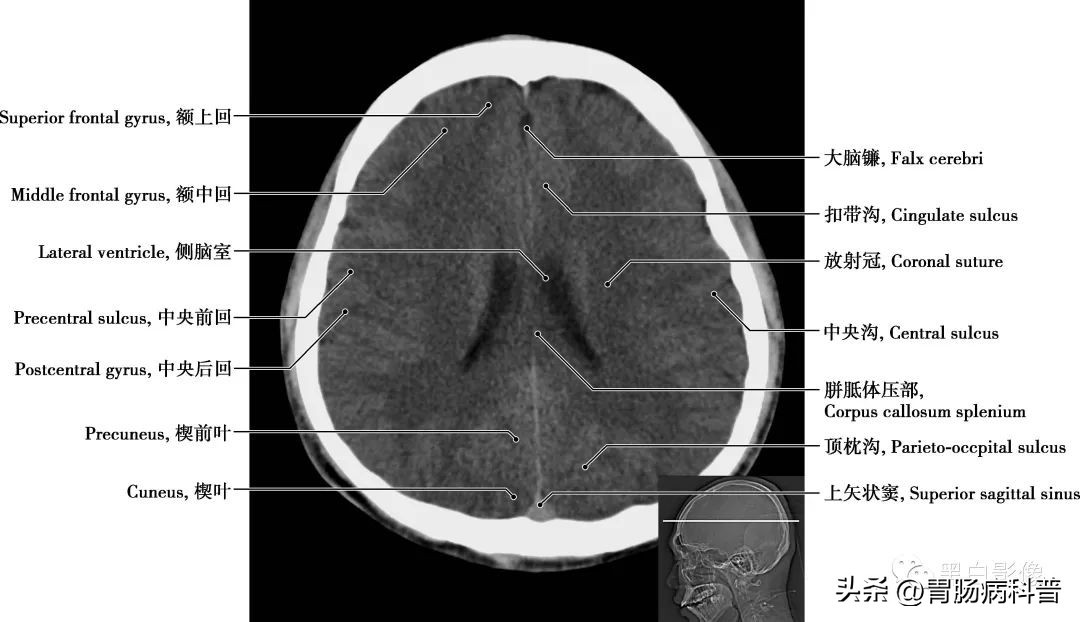

图1-1-7 经侧脑室体部轴位切面

侧脑室 由额角、体部、颞角、枕角组成,额角和体部的内侧壁为透明隔,胼胝体和额角密切相关,胼胝体的下方和膝部形成了侧脑室前角的顶部和侧壁,室间孔为前角的后界,侧壁是尾状核头的中间区。楔叶 距状沟将枕叶分为上下两回,上方为楔叶,其前界为顶枕沟,楔叶视皮质接受双眼同侧半上部视网膜束的冲动